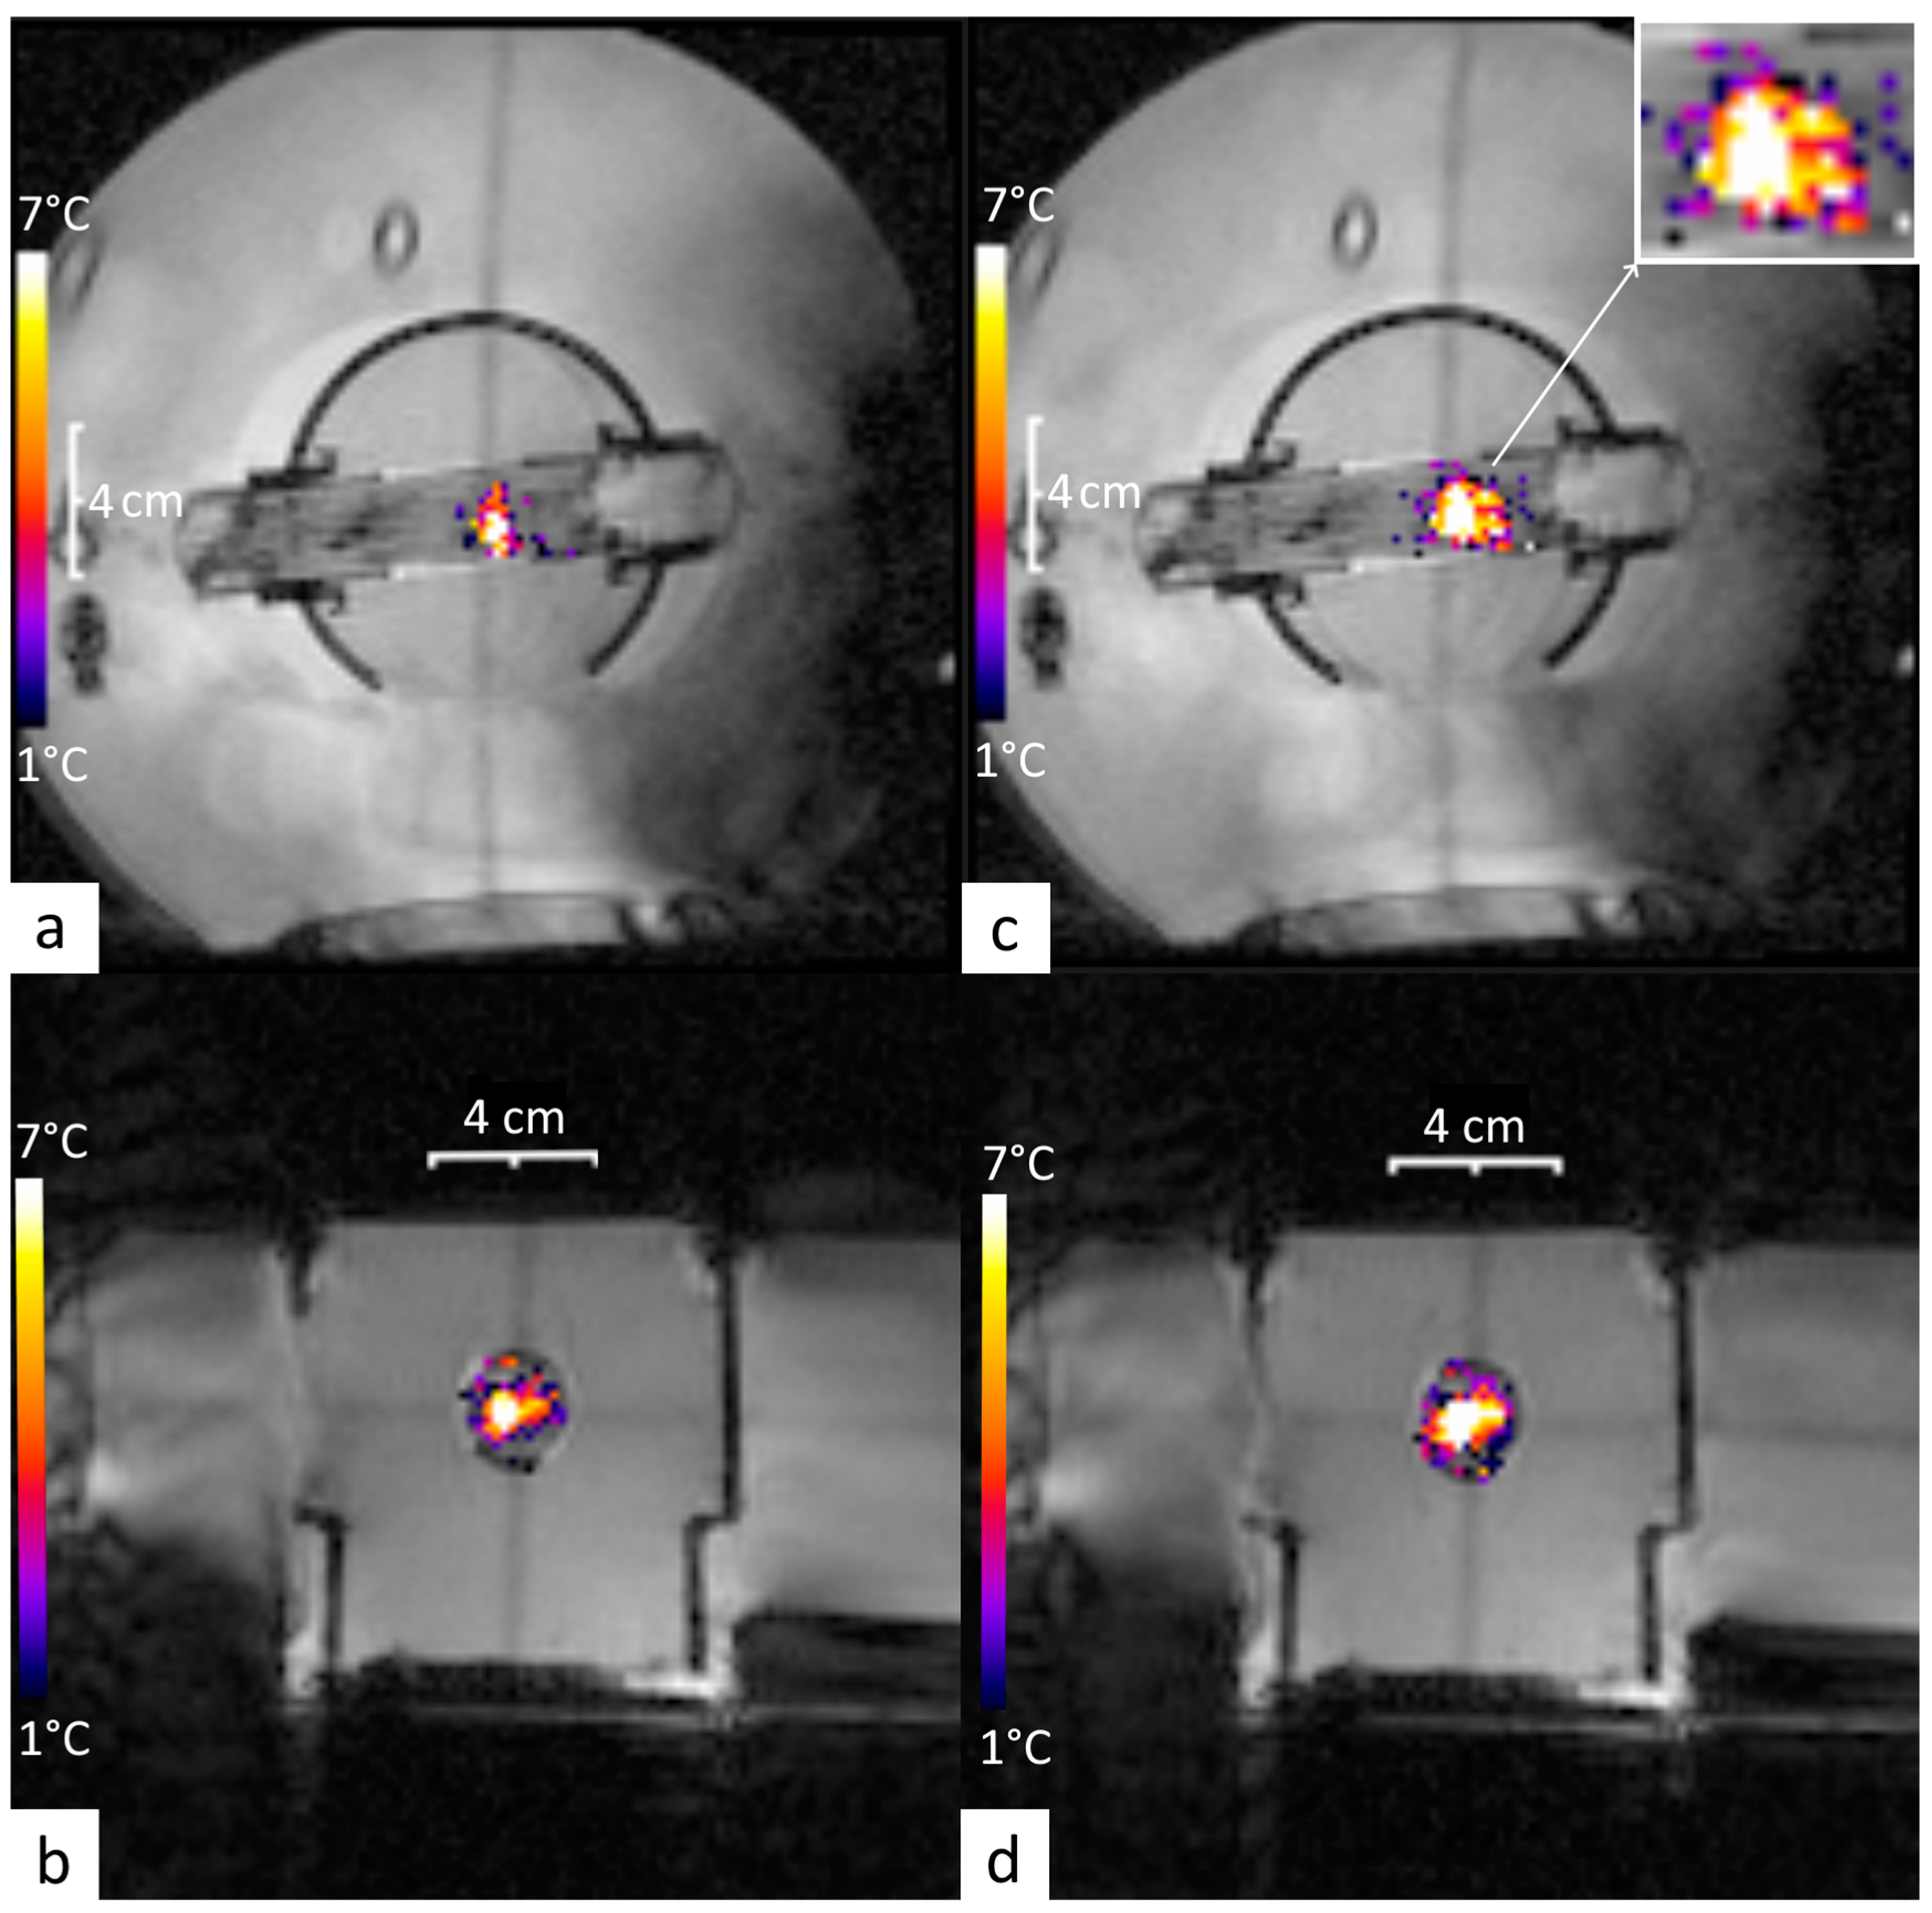

3.1. Off-Line Hyperthermia Control in Perfused Phantoms

3.2. Conventional On-Line Control Loop Versus the New Approach Using the Impulse Response Formalism